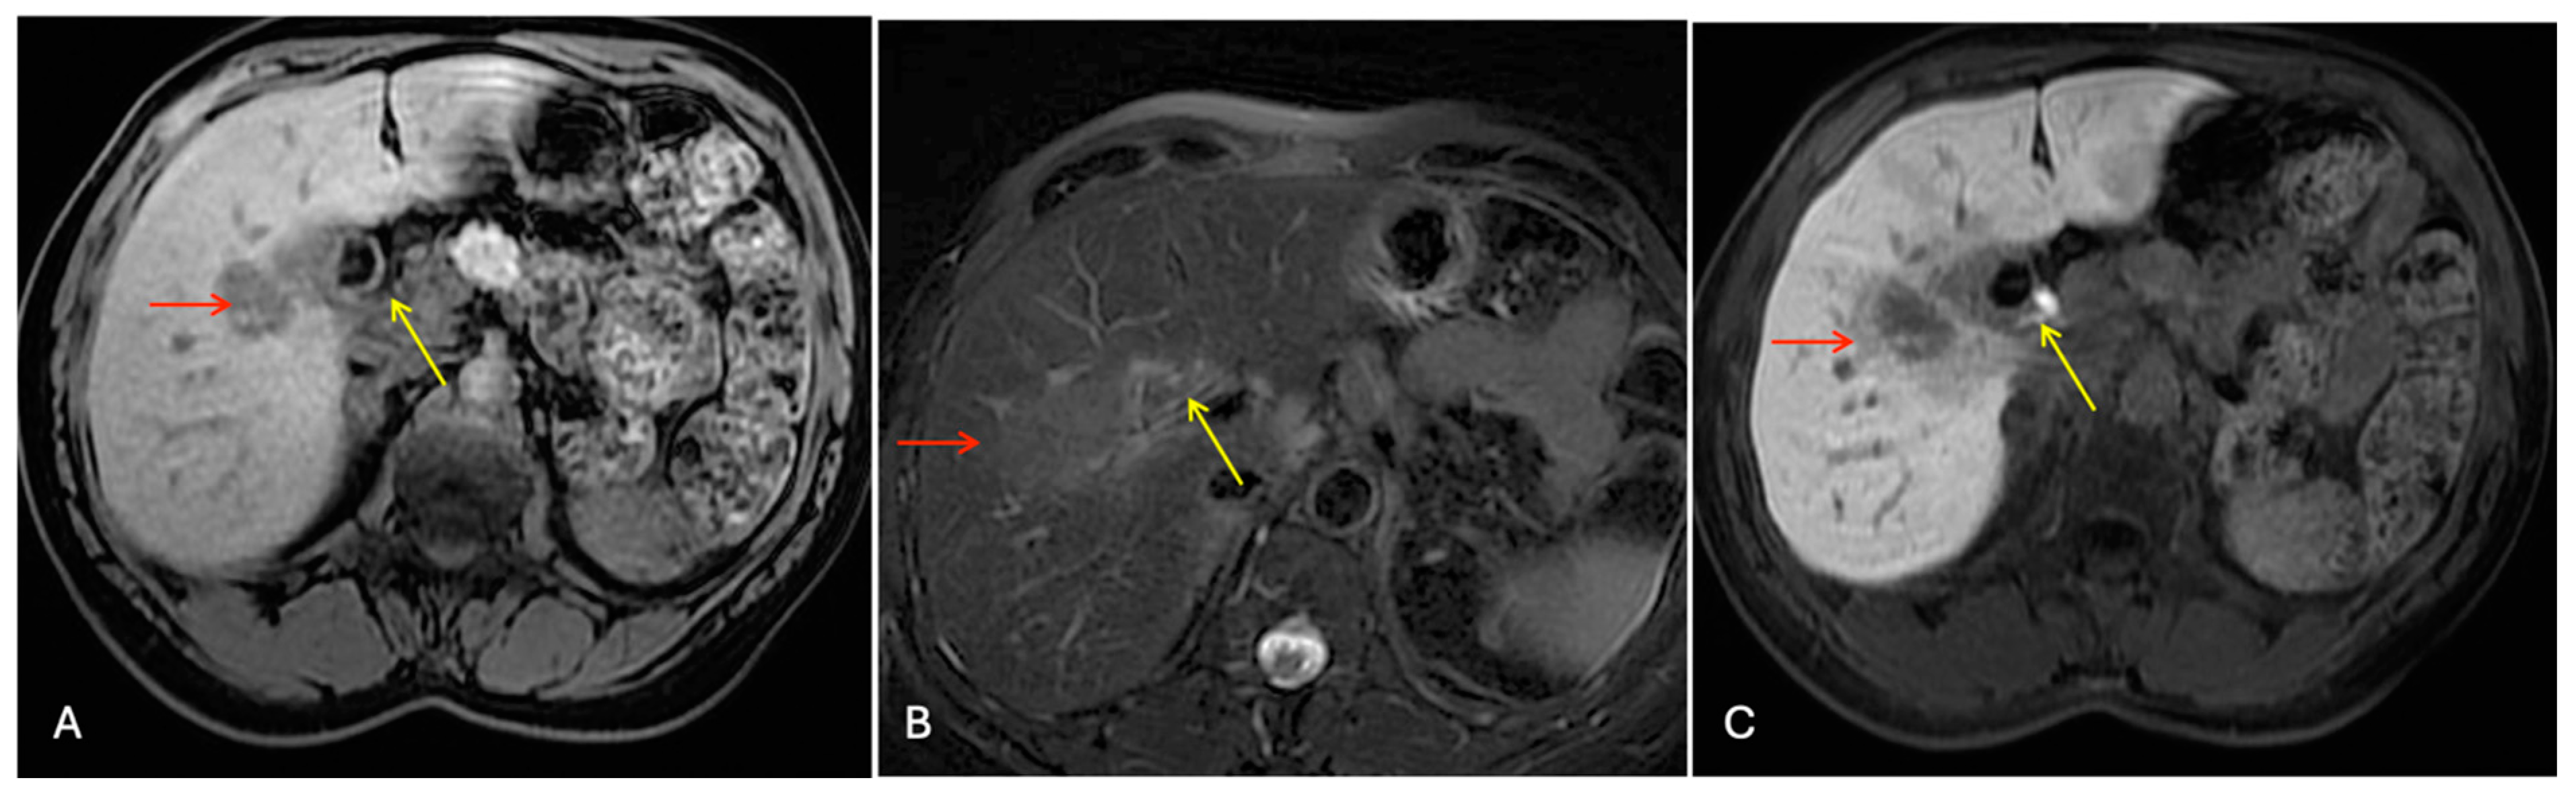

The abdominal ultrasound mentioned multiple small gallstones with initial wall thickening and without biliary tree dilation. Next to the gallbladder in S5, a 35 mm hypoechoic mass was revealed. Gd-EOB-DTPA-enhanced magnetic resonance imaging (MRI) showed a 40 mm tumor with a low intensity on the T1-weighted images, a light high intensity on the T2-weighted images, and a low intensity on the hepatobiliary phase, highly suspected to be ICC (Figure 2).

Figure 2.

Sequential dynamic contrast enhancement liver MR images. Liver mass in segment 5 (red arrow), gallbladder (yellow arrow): (A) hypo-intensity in T1 phase, (B) faintly hyper-intensity in T2 phase, and (C) hypo-intensity in hepatobiliary phase.